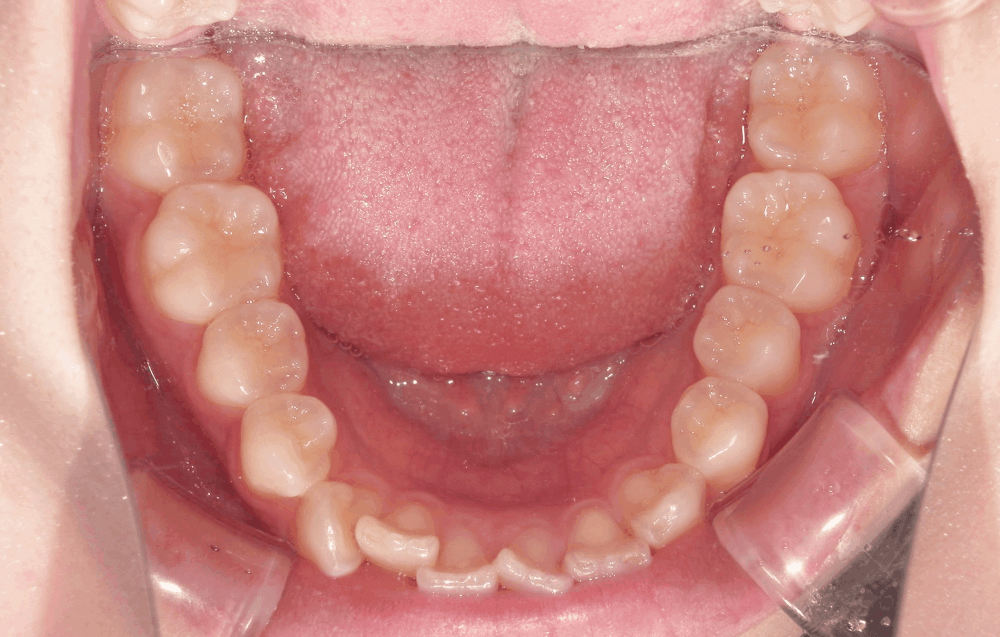

<初診時>

上の前歯の横の歯(前から2番目)が前方に飛び出しており、全体的にガタつき(叢生)が見られます。これは、歯の大きさに対してあごの幅がやや狭く、歯がきれいに並ぶスペースが足りないために起こります。

また、上下の前歯の中心(正中線)がわずかにずれており、奥歯のかみ合わせやあごの位置の影響がみられました。

- 中程度の叢生(ガタガタ)

- 正中線のずれ